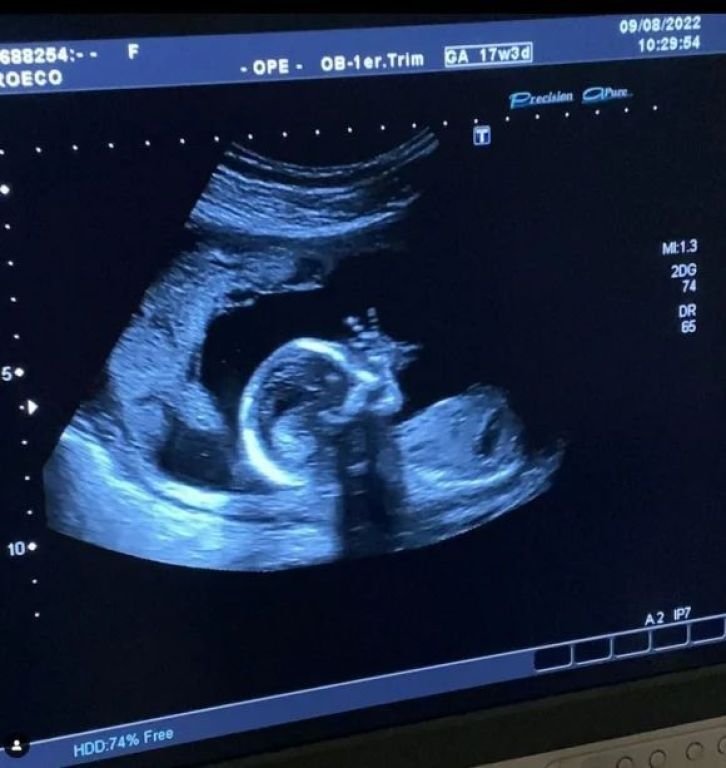

¡Para morir de ternura! Cande Ruggeri compartió la primera ecografía de su beba

A través de su cuenta en Instagram, por el Día de la Niñez, que se celebró el pasado domingo, Cande publicó la imagen del eco que recibió cientos de comentarios de sus seguidores, ya que es una de las primeras ecografías de la beba y se la pudo ver levantando una de sus manitos.

En la publicación, la modelo escribió: "Amor y paz para este día de la niñez". Asimismo, no tardaron en llegar mensajes por parte de los usuarios de la red social:"Esa es la mano amiga? Keeee no no no", "que lindo felicidades", "me derrito", "Parece un caracol".